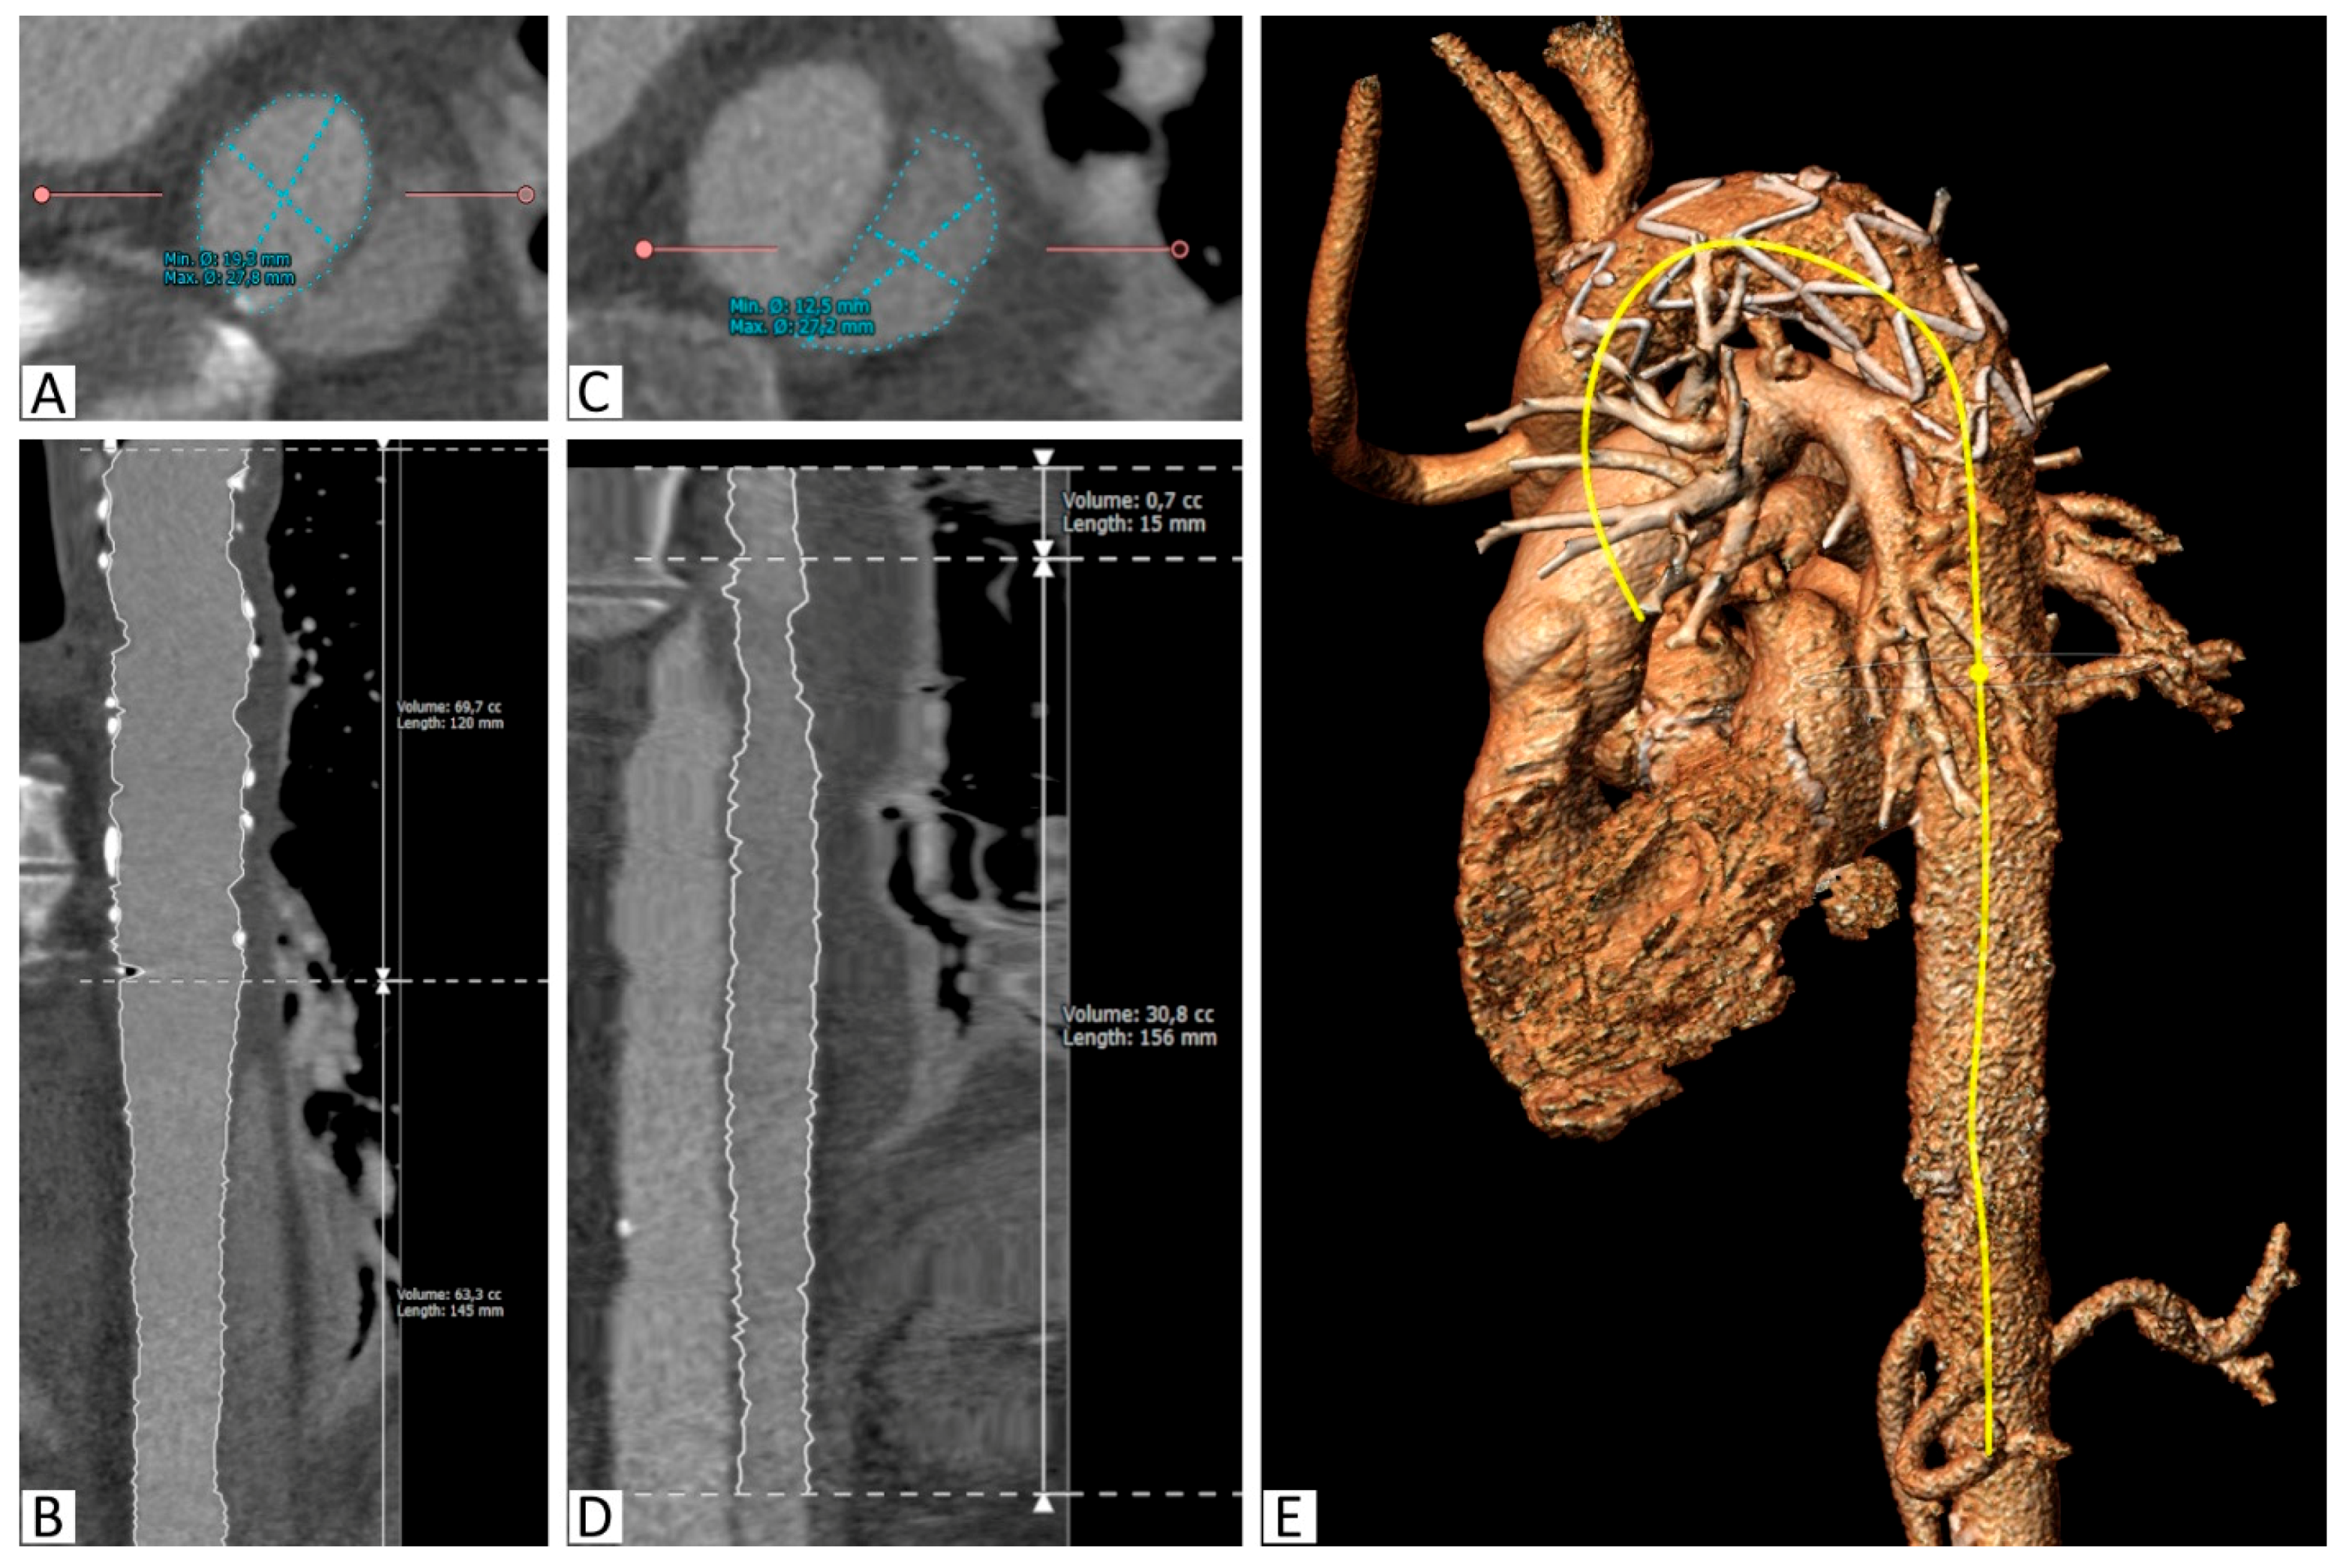

Figure 2.

Segmentation of the aorta with the implanted stent. (A): Segmentation of the true lumen in the descending thoracic aorta distal to the stent graft on a reconstructed slice orthogonal to the vessel, (B): Curved multiplanar reconstruction of the true lumen between the proximal stent graft and the celiac trunk, including length and volume calculations, (C): Segmentation of the false lumen in the descending thoracic aorta distal to the stent graft on a reconstructed slice orthogonal to the vessel, (D): Curved multiplanar reconstruction of the false lumen between its origin in the stent graft and the celiac trunk, including length and volume calculations, (E): 3D reconstruction with the semiautomatically created center-line (yellow).